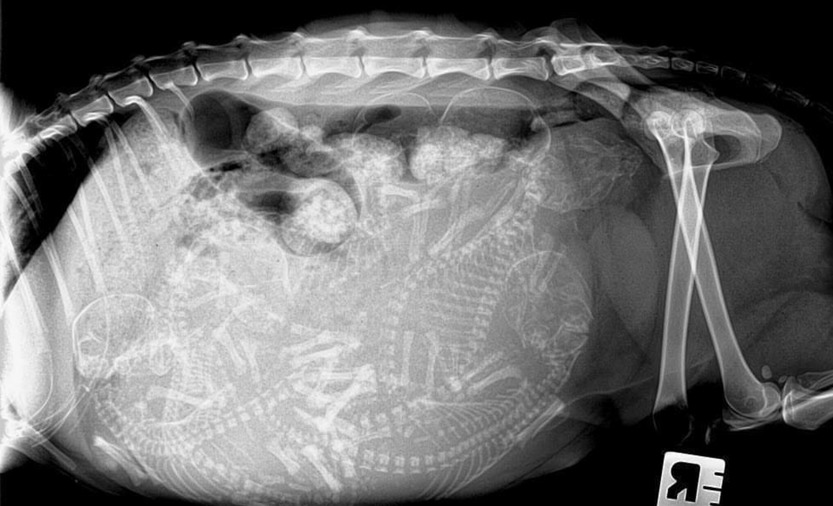

If all the previous points have been successfully completed, and the new couple is ripe for the creation of a feline family, then the process of pregnancy of the cat begins. The process is slow, requiring patience and special care not only for the female, but also for her future offspring. The period of gestation of exotic animals is up to 65 days plus or minus 1-2 days. It is noted that kittens that were born in the period of 50-58 days, usually die immediately.